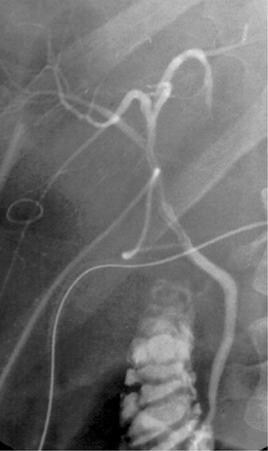

CJ is usually indicated for patients with diseased extrahepatic bile ducts (primary sclerosing cholangitis, cholangiocarcinoma, biliary atresia); prior biliary surgery; size disparities between donor and recipient ducts; reduced-size, split, and living donor grafts ( Fig. 76-1 ); retransplantation; or when the blood supply to the distal donor bile duct is suboptimal. CJ is the most common anastomosis used in pediatric liver transplant patients because of the small size or absence of bile ducts in this patient population. Problems and potential complications unique to Roux-en-Y CJ include increased surgical time, stricture or leakage of the CJ, bleeding at the jejunojejunostomy, bowel ischemia, Roux limb torsion, intestinal perforation, delayed mixing of bile with intestinal contents, altered cyclosporine absorption, and cholangitis induced by reflux of intestinal pathogens. In addition, creation of CJ restricts endoscopic evaluation of the biliary system, occasionally requiring percutaneous transhepatic cholangiography (PTC). Because magnetic resonance cholangiography (MRC) has emerged as a sensitive, noninvasive diagnostic tool, CJ-related diagnostic problems are likely to decrease.

FIGURE 76-1, Complex biliary reconstruction using a combination of duct-to-duct and bilioenteric anastomosis in a patient who received a right hepatic lobe from a living donor. A, Duct-to-duct reconstruction of two orifices of the right lobe graft with the ductus choledochus of the recipient. The image was performed on the fifth postoperative day depicting a regular biliary anastomosis. B, In a second step, contrast medium was given via the transintestinal internal drainage stenting a bilioenteric anastomosis established for draining a separate orifice. The residual contrast medium applied via the T tube is still visible in the background.

The epidemiology and spectrum of BCs have also changed over the past decade because of the establishment of split-liver transplantation and reduced-size liver transplantation. The incidence of BCs in reduced-size liver transplantation was reported to be as high as 24%, however, with approximately 50% of complications related to cut-surface leakages. The initial experience with ex situ split-liver transplantation for infants and children resulted in an average biliary complication rate of 24% to 27%. Meanwhile, complication rates for ex situ split OLTs have been markedly reduced. In situ split OLT was reported to result in lower complication rates of the biliary system of about 0% to 15%, reflecting the better anatomical orientation during the in situ splitting process. In pediatric recipients a biliary complication rate of 8.7% to 15% was reported. A further modification has been seen with the advances in adult-to-adult LDLT. The incidence of BLs and BSs was reported to be as high as 30% in the early phase and may be attributed to initial difficulties in defining the dissection plane around the right hepatic duct and complex reconstructions including several orifices ( Fig. 76-2 ; see Fig. 76-1 ). A similar development has taken place in pediatric LDLT.